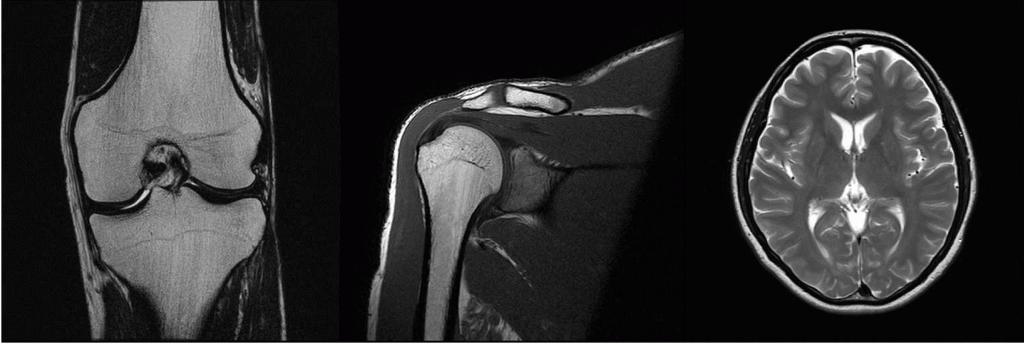

MRI装置

1.5テスラMRI装置です。MRI検査では、強い磁場と高周波を使用して、体内にある水素原子核を磁気に共鳴させて電波を発生させます。その電波を受信する事により、体の色々な方向の断面の画像を作成することが可能で、様々な病気の発見に優れています。

当院に導入したMRI装置は、1.5 テスラの磁場強度を有する装置で、質の高い診断が可能となっております。